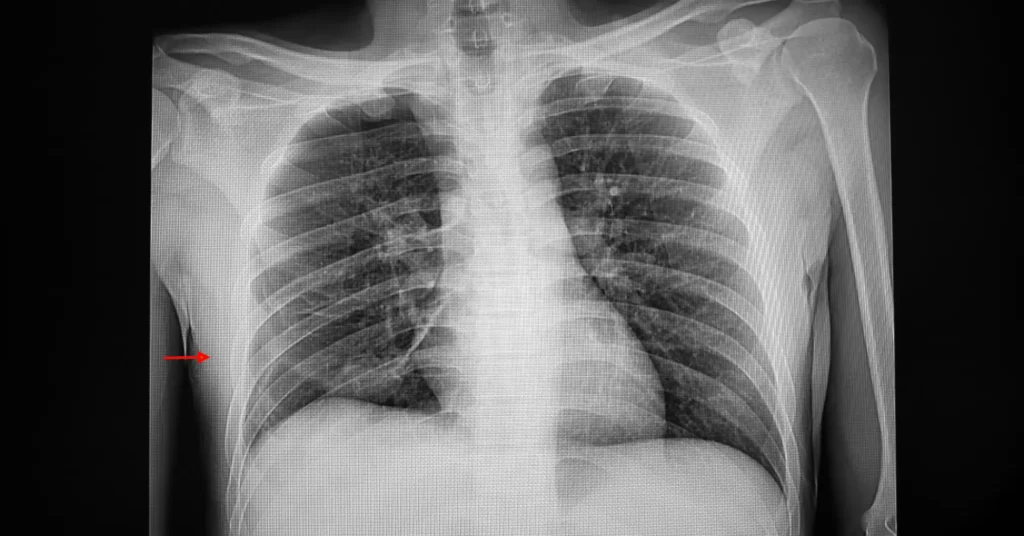

Para confirmar el diagnóstico se utilizan pruebas de imagen como:

- Radiografía de tórax

- Tomografía computarizada (TC)

- Ecografía pulmonar

Estas pruebas permiten visualizar la presencia de aire en el espacio pleural y el grado de colapso pulmonar.